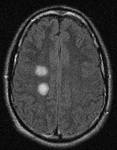

Séries de imagens de ressonância nuclear magnética (RNM) do cérebro de um paciente com encefalomielite disseminada aguda: centro semioval

Do acervo pessoal de Catalina C. Ionita, MD; usado com permissão